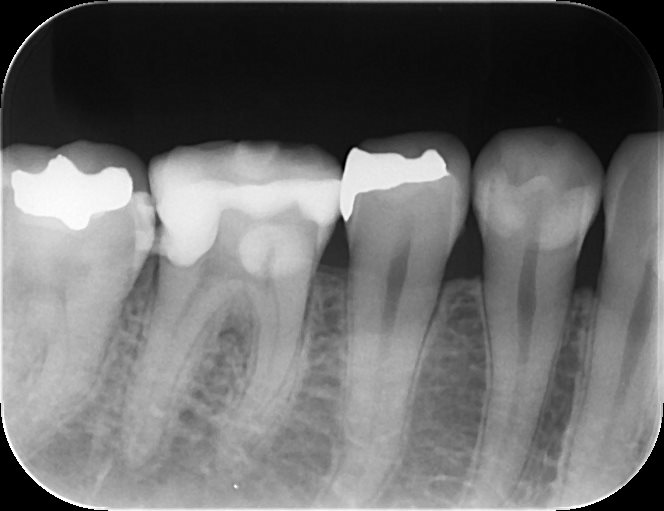

レントゲンを撮影し、状況を説明。

根管治療が必要なことを伝え、最終補綴物はセラミッククラウンで治療していくことになりました。

根管治療後のデンタルX戦写真